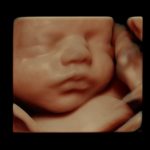

The pregnancy process, which is described as an extremely exciting expectation for parents, is also a period that requires close monitoring of maternal and infant health. One of the most important instruments that assist obstetricians in the follow-up process is imaging systems. During the examination, which usually starts from the 6th week of pregnancy, ultrasound imaging continues throughout the entire pregnancy period and sheds light on the experts about the development of the baby and the detection of extraordinary developments. Unlike the applications performed with 4D ultrasound systems between the 19th and 23rd weeks of pregnancy, thanks to Voluson E8, which provides much more detailed imaging thanks to its superior technology, possible anomalies in the baby can be detected more clearly or the health of the baby is ensured.

Talking about the advantages of Voluson E8, Prof. Dr. Müfit C. Yenen said, “The structure of the vessels has become easily visible and easier to diagnose thanks to the fast and easy imaging opportunity provided by E8 technology even in the thinnest and smallest vessel structures. Even the blood flow in the vessels has become visible. The shapes in the anatomical structure of the baby, whose development process continues in the womb, can be easily displayed thanks to the advanced volume contrast feature of the device. Critical measurements such as height, weight, head circumference and nuchal thickness, which are accepted as important indicators of baby's health, are made automatically by the device. Thus, the possibility of error in manual measurements has now been eliminated. Thanks to the technological superiority of the system, which also makes it possible to display the internal structures of the baby, extraordinary anatomical realism is provided in the images obtained.”